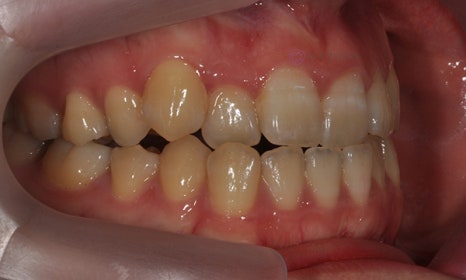

다음 케이스 역시 위 아래 치아의 중심선 차이가 있으며, 덧니 및 반대교합이 관찰되었습니다. 위 치아의 중심선도 얼굴의 중심선과 일치하지 않고 우측(사진 상 왼쪽)으로 틀어져 있었습니다. 본 환자는 발치를 하지 않고 치아를 뒤로 이동시켜서 치아의 중심선도 맞추고 얼굴의 중심선과도 맞추었습니다.

2020.1

교정 마무리 후 위 치아의 중심선은 얼굴의 중심선과 일치하였으며, 위 아래 치아의 중심선도 일치하였습니다.

2022.7